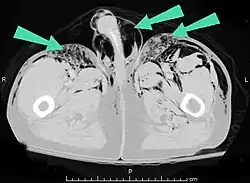

Air can be trapped under the skin in necrotizing infections such as gangrene, occurring as a late sign in gas gangrene,[2] of which it is the hallmark sign. Subcutaneous emphysema is also considered a hallmark of Fournier gangrene.[27] Symptoms of subcutaneous emphysema can result when infectious organisms produce gas by fermentation. When emphysema occurs due to infection, signs that the infection is systemic (i.e. that it has spread beyond the initial location) are also present.[9][21]